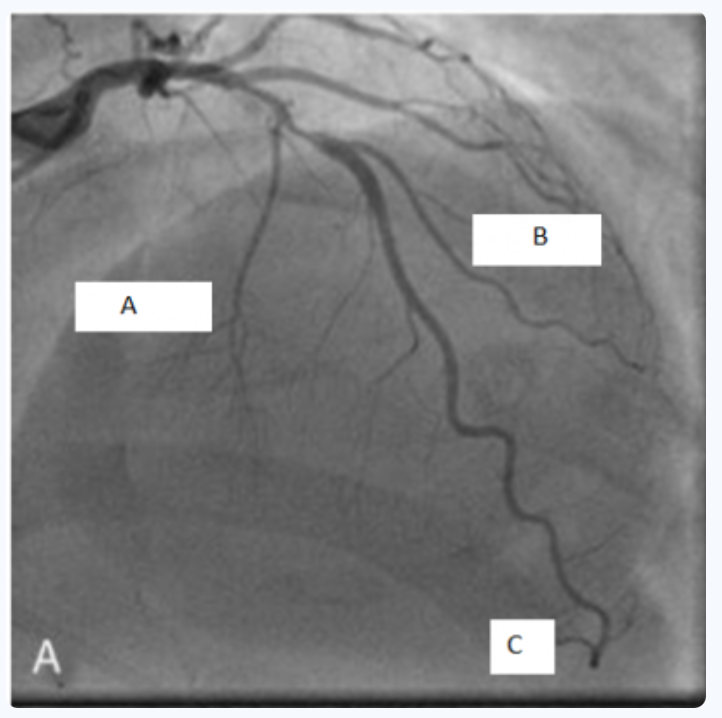

Concernant cet examen : (cf photo)

C’est bien une coronarographie.

Le B correspond à une diagonale !